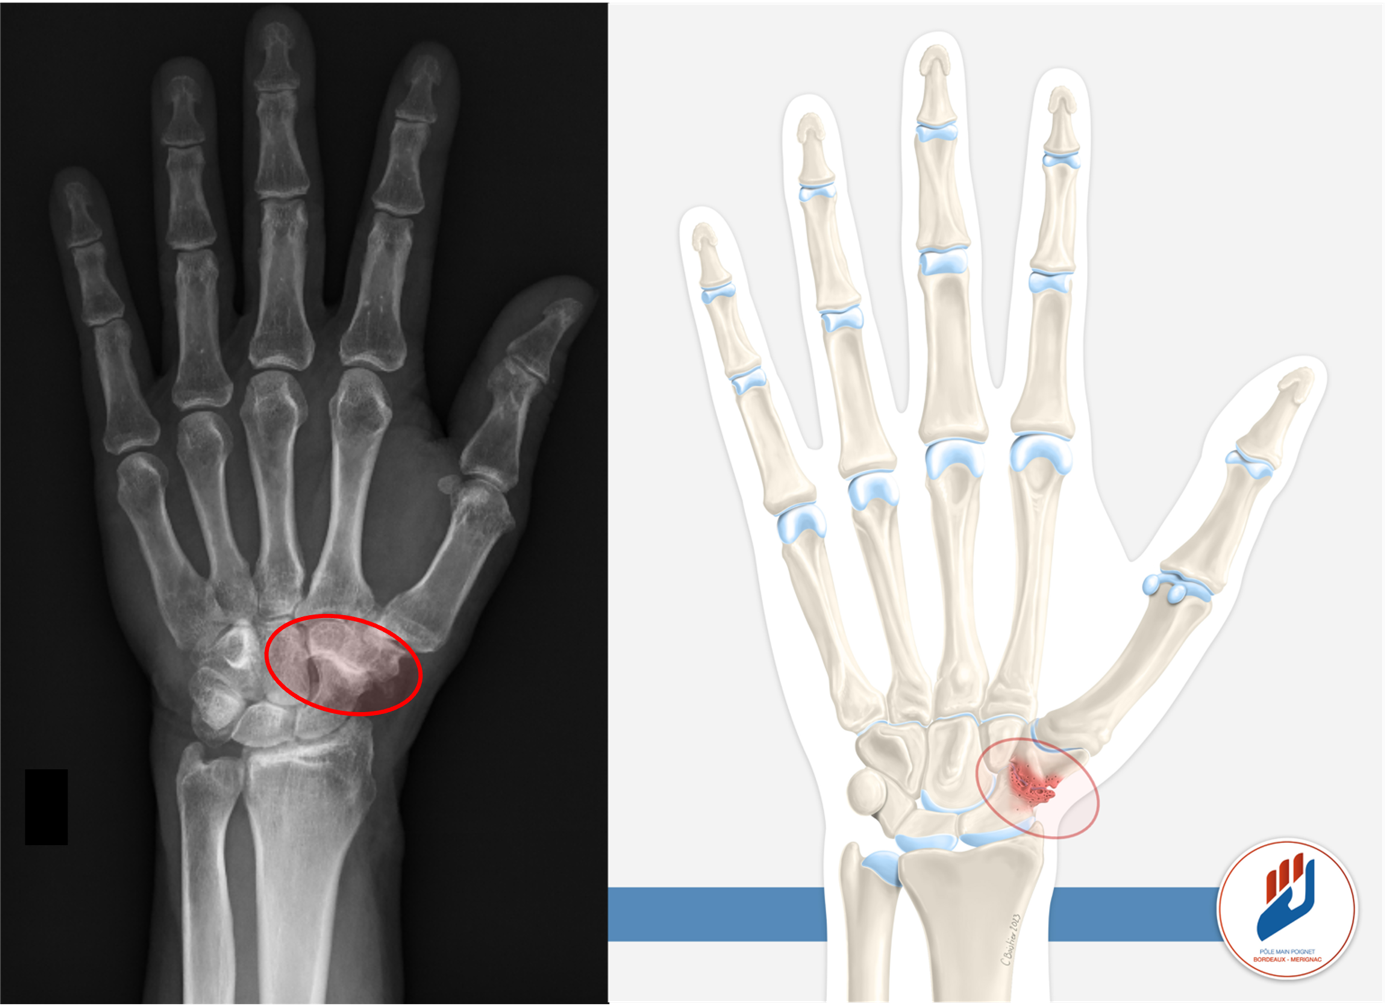

L’arthrose scaphotrapézo-trapézoïdienne, plus connue sous le nom d’arthrose STT, est une cause fréquente de douleur du poignet et de la base du pouce. Elle touche l’articulation située entre le scaphoïde et deux os de la base du pouce, le trapèze et le trapézoïde. Cette zone est essentielle pour la fonction et la mobilité du poignet et du pouce. Lorsque cette articulation s’use, les gestes de la vie quotidienne deviennent douloureux et gênants, on parle alors d’arthrose Scapho-Trapèzo-Trapèzoïdienne (STT).

Le diagnostic d’arthrose STT repose sur l’examen clinique réalisé par un chirurgien de la main. La localisation de la douleur et sa reproduction à certains mouvements sont caractéristiques. Les radiographies du poignet permettent de confirmer l’arthrose et d’évaluer son importance. Un scanner peut être prescrit pour analyser précisément l’articulation et orienter le traitement.